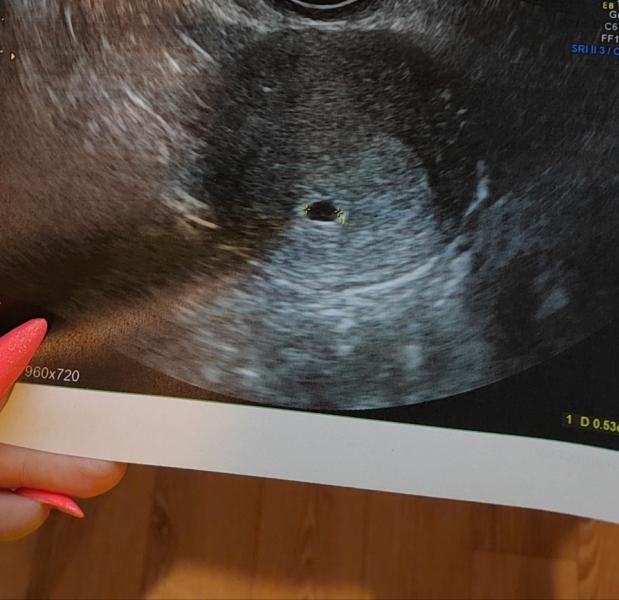

Вот эта точечка, это и есть малышочек?) всегда интересно как там на УЗИ видно и разглядывают 🤣🤗

Я до последнего думала, что у меня сбой гормональный, но когда врач на узи,начала говорить размер плода 4,9 мм, все сомнения улетучились.